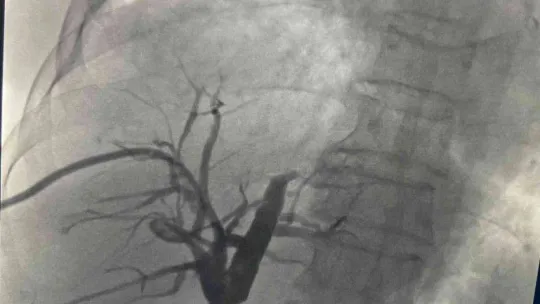

Prof. Dr. Ercan Kocakoç, bu yeni yöntemin tıp literatürüne Radyofrekans (RF) ablasyon olarak geçtiğini belirtti. Başta karaciğer olmak üzere vücudun birçok bölgesindeki tümörlerin ultrason, tomografi gibi görüntüleme yöntemlerinin kılavuzluğunda yakılarak tedavi edebilen, girişimsel radyolojik bir yöntem olduğunu söyledi. Prof. Dr. Ercan Kocakoç, önce safra kanalı içerisine basitçe ince plastik bir hortum yerleştirilerek, biriken safra sıvısının dışarıya alındığını dile getirerek, “Tümörün olduğu bölgedeki darlık, bir tel yardımıyla geçilebilirse önce balon ile bu bölge genişletilmeye çalışılır. Sonrasında ise stent denilen ince tellerden örülü metalik bir küçük borucuk yerleştirilerek dışarıda hortum olmadan safranın on iki parmak barsağına akması sağlanır” dedi.

Prof. Dr. Ercan Kocakoç ayrıca safra yolu kanserlerinin tedavisinde Endobiliyer RF ablasyon yöntemi ile de safra kanalı içerisindeki tümörün RF ablasyon ile yakıldığını kaydederek, “Bu yöntemde safra kanalındaki darlığın balon ile açılması, safra kanalı içerisinden RF (radyofrekans) ablasyon ile tümörün yakılması ve safra kanalına metalik stent yerleştirilmesi aşamaları vardır. Bu işlem safranın on iki parmak bağırsağına akmasını sağlayarak sarılıksız daha uzun bir ömür geçirilmesine katkı sağlar” şeklinde konuştu.